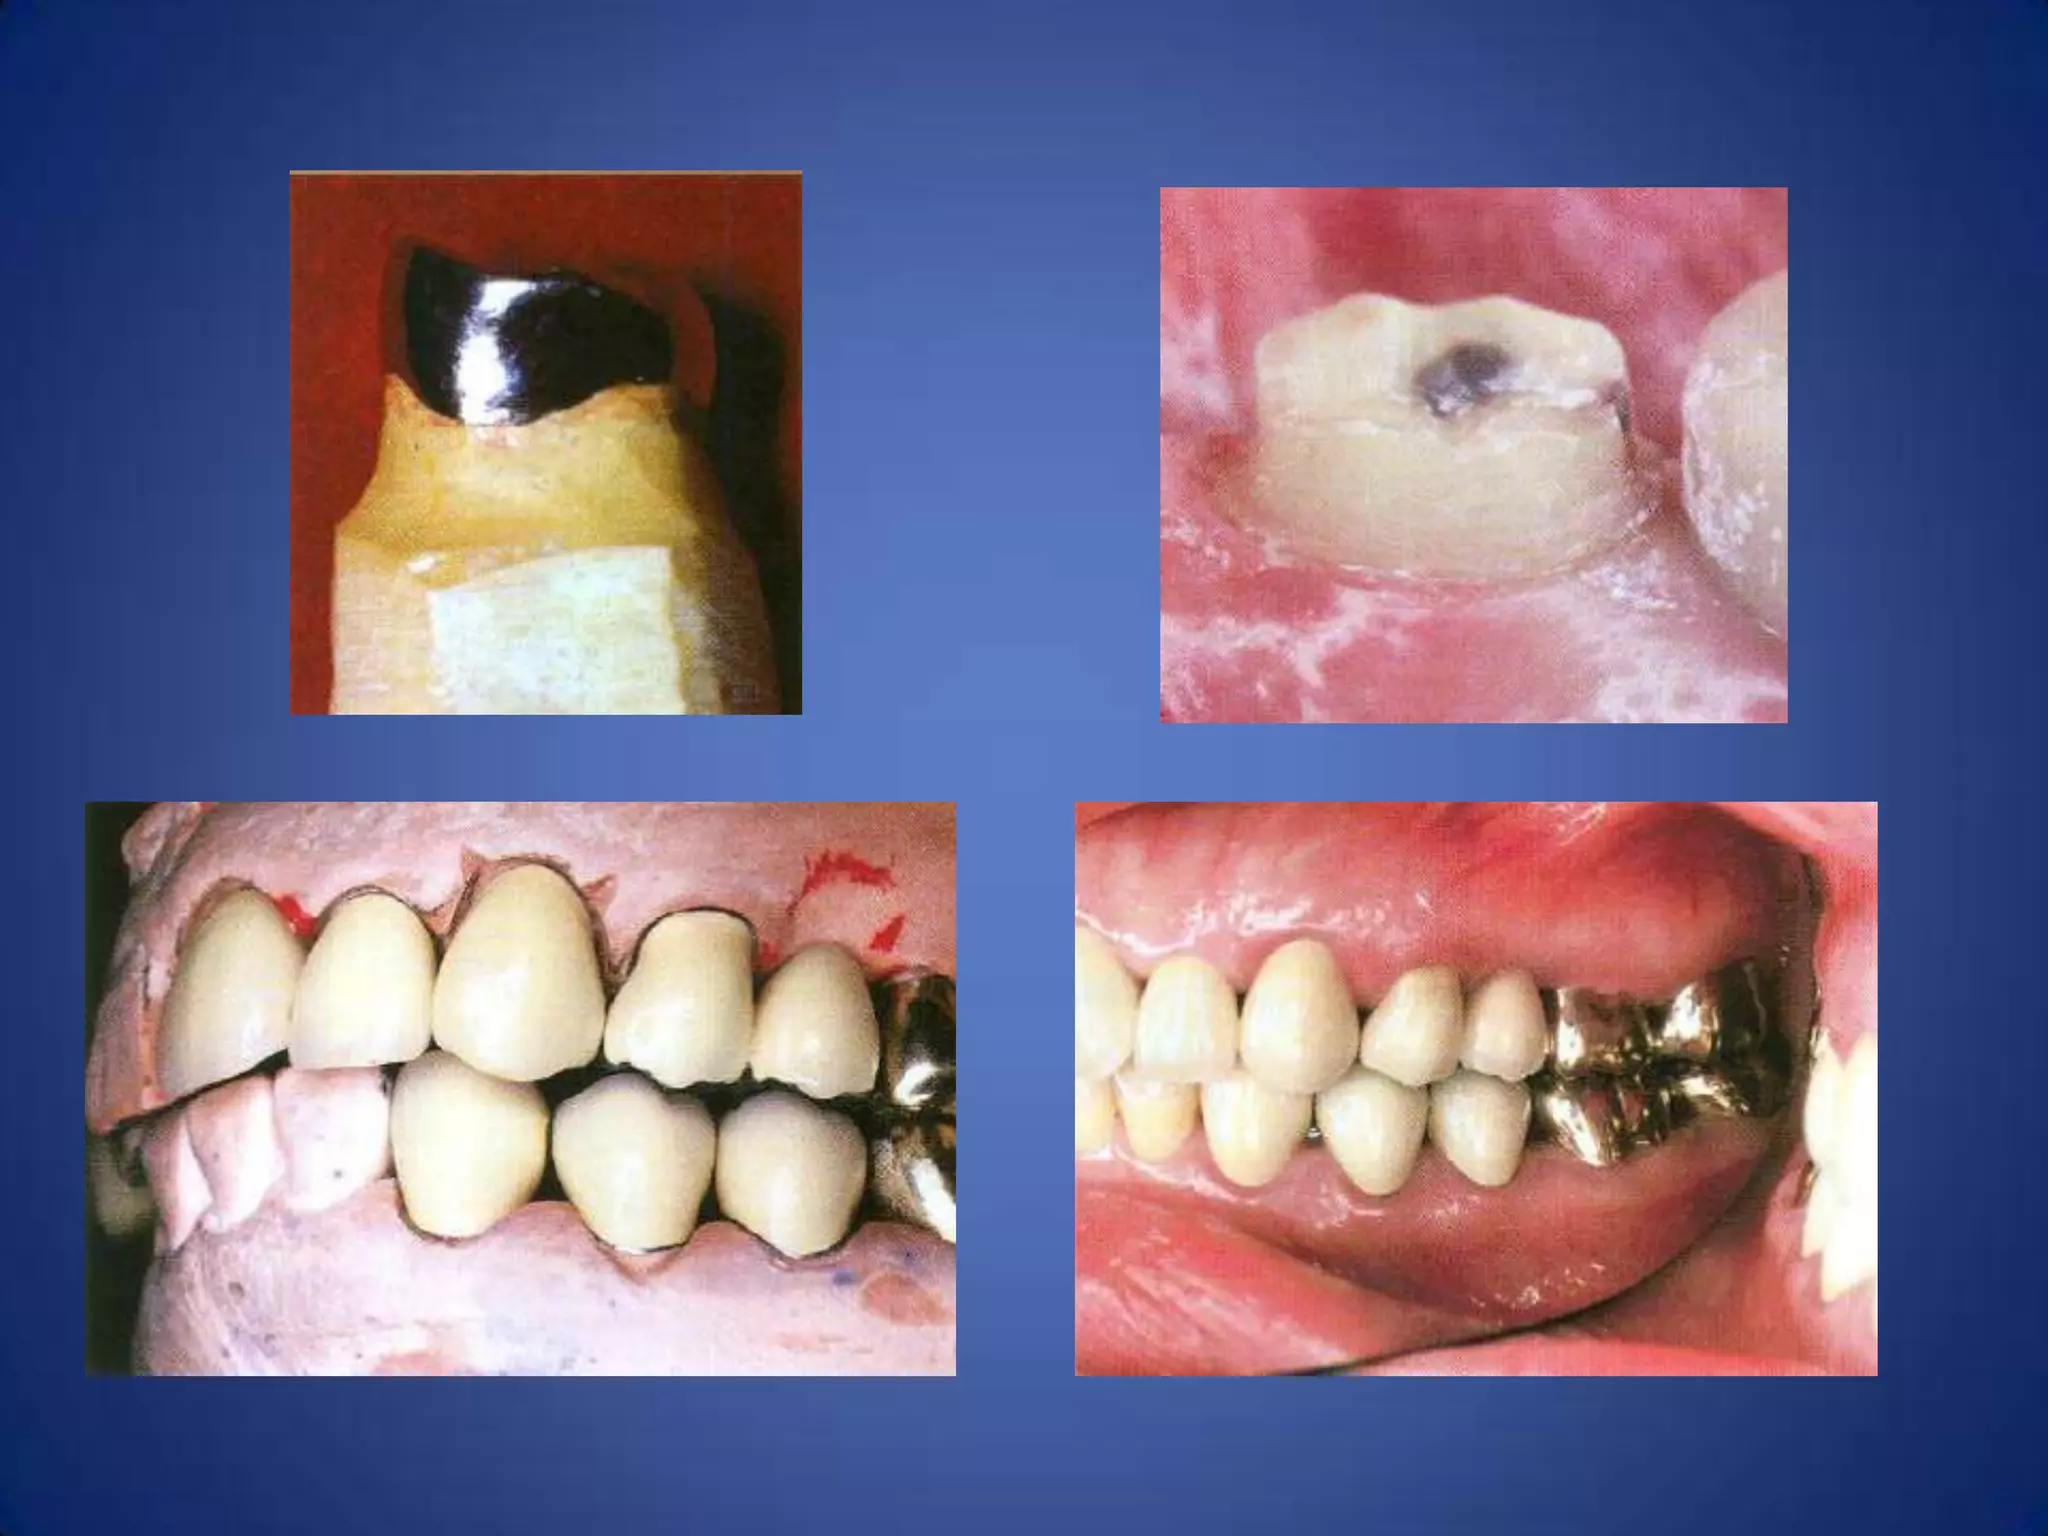

On of the most common violation of

this principle is seen in discriminate use

of full porcelain coverage in a situation

when partial veneer coverage can be

used

Avoidance of over contour

• Gingival inflammation is commonly associated with crowns and

FPD abutments having excessive axial contours, probably because it

is more difficult for the patient to maintain plaque control around

the gingival margin. A tooth preparation must provide sufficient

space for the development of good axial contours.

• Under most circumstances a crown should duplicate the contours

and profile of the original tooth (unless the restoration is needed to

correct a malformed or malpositioned tooth). If an error is made, a

slightly under contoured flat restoration is better because it is

easier to keep free of plaque; however, increasing proximal contour

on anterior crowns to maintain the interproximal papilla may be

beneficial.

• Sufficient tooth structure must be removed to allow the

development of correctly formed axial contours, particularly in the

interproximal and furcation areas of posterior teeth, where

periodontal disease often begins